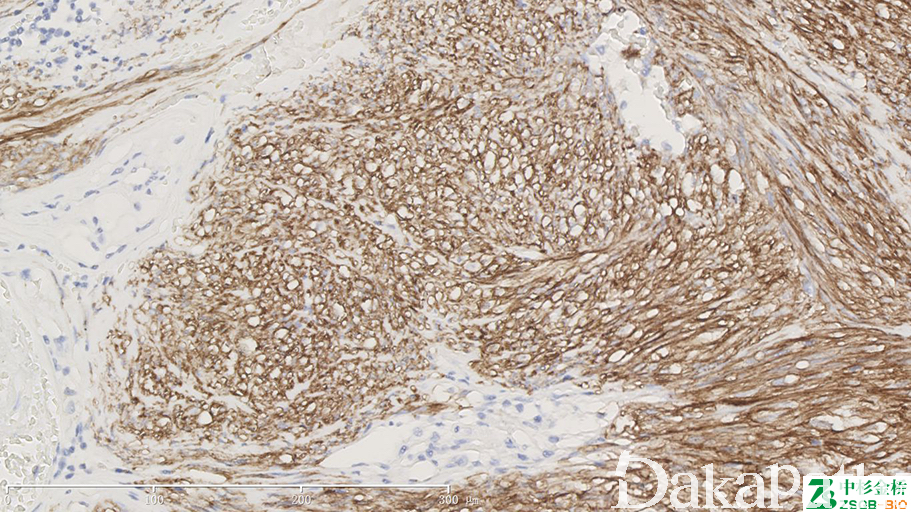

DOG1 基因(aka TMEM16)位于染色体 11q13,含有 26 个外显子,编码 960 个氨基酸组成的 114kDa 的蛋白,功能不详,其蛋白结构具有 8 个穿膜功能区。DOG1 蛋白选择性地表达于胃肠道间质瘤,与 KIT/CD117 相比,无论对于具有 KIT 基因突变还是 PDGFRA 基因突变的胃肠道间质瘤,,DOG1 都是 GIST 更加敏感和特异性的标记物。可以使更多的病人能 够获得接受靶向治疗(如伊马替尼)的机会。

胃肠道间质瘤的诊断。

通常阳性(<95%,≥75%的病例阳性): 胃肠道间质瘤、胃肠外间质肿瘤